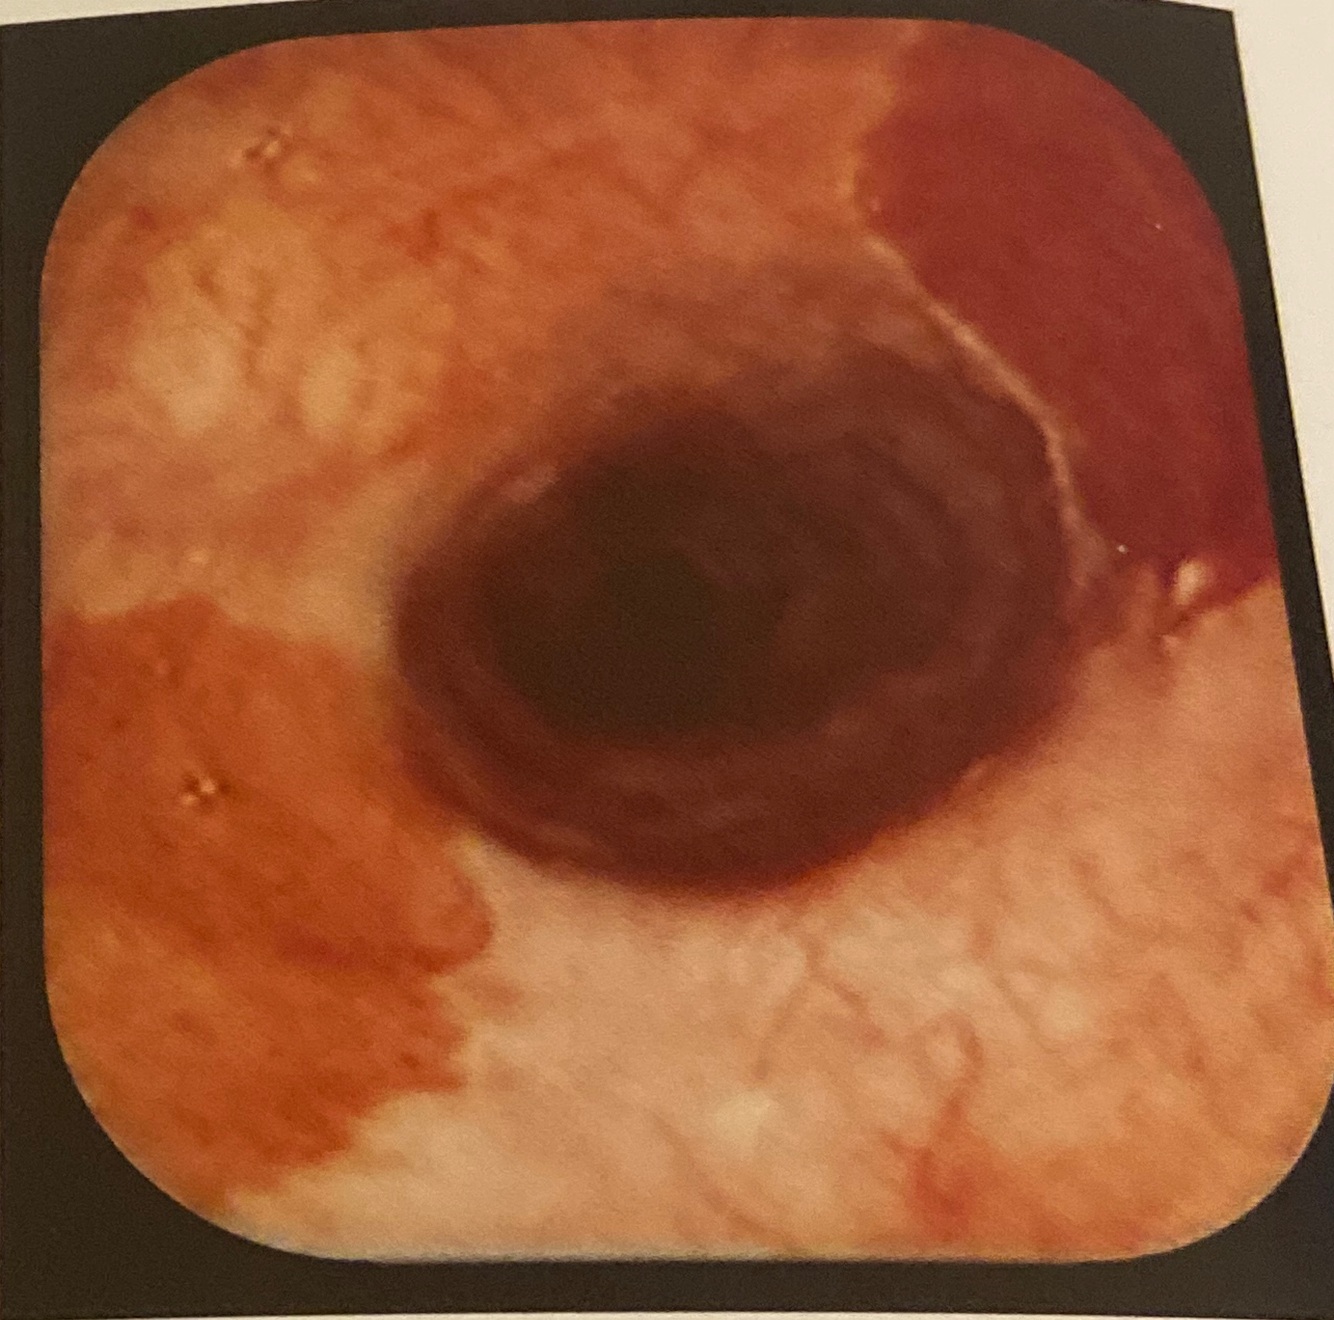

Esofagite _______.

tuberculosa. Úlcera pouco profunda com base necrótica e margem mal delimitada